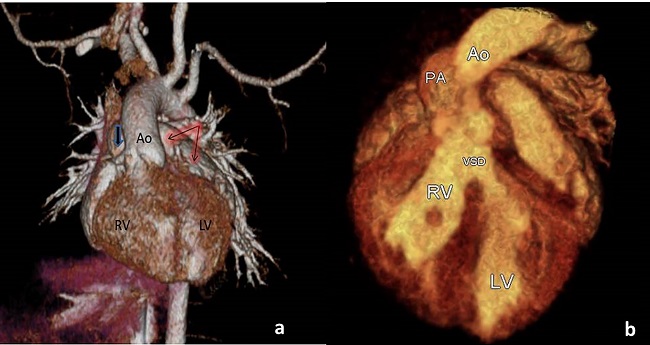

A 15-day-old newborn male was referred to our clinic for further evaluation of central cyanosis and previously detected heart murmur. Prenatal history was unremarkable with uneventful full term labour. During the initial physical examination, the baby was slightly cyanotic (SpO2: 88-90%) and the cardiac auscultation revealed a grade II systolic murmur at the upper left sternal border. Four extremity pulses were regular with approximate blood pressure results. The electrocardiogram was consistent with possible right ventricular hypertrophy and the chest X-ray demonstrated cardiomegaly due to enlarged right cavities, flat pulmonary trunk segment, and diminished pulmonary vascular markings. The transthoracic echocardiography revealed situs solitus, levocardia with normal pulmonary venous drainage, and atrioventricular concordance. Ventriculo-arterial relations were supplied by both the entire pulmonary trunk emerging from the right ventricle along with more than 50% of the aorta. DORV with anterior and left-sided aorta was evidenced (Figures 1A and 1B). Secundum type atrial septal defect of 10 mm in two-dimensional images maintaining left to right shunt, subaortic VSD approximately 9 mm in diameter with mostly left to right bidirectional flow, and right ventricular outflow tract obstruction originating from the subvalvular region generating a transpulmonic gradient of 50 mmHg were also noted. Both the left and right ventricular systolic functions were evaluated as preserved. There was no obstruction of the aortic arch and the pericardium had a normal appearance. For more detailed evaluation of the cardiac anatomy, cardiac computed tomography was performed (Figures 2A and 2B). The final diagnosis was DORV with situs solitus, D-loop ventricles, and L-position of the aorta {S,D,L}, left aortic arch associated with a large subaortic VSD, and pulmonary stenosis. Although the weight gain of the patient was sufficient with an uneventful follow-up, decremental course of the systemic saturation clarified the necessity of a surgical intervention at the age of six months. Surgery was performed via standard median sternotomy, and ascending aortic + bicaval cannulations were initiated afterwards. Anatomical relationship between the great vessels and intracardiac defects was coherent with the echocardiography. Additionally, juxtaposition of the right atrial appendage to the left and the sinus node artery passing through the anterior aspect of the right ventricular epicardium were also noticed perioperatively. DORV repair, including the Rastelli procedure (VSD closure with porcine pericardium, right ventricle-pulmonary trunk conduit: 14 mm Contegra® Medtronic, Inc. Medtronic Parkway Minneapolis, United States of America) and cessation of the antegrade flow by over-and-over suture technique, was performed. The postoperative course was uneventful, and the patient was discharged from the hospital on the postoperative 10th day. The proceeding follow-ups were free of problems.

As the anatomy of DORV patients are complicated with different additional pathologies, echocardiography is an indispensable tool on the way to diagnosis, providing the fact that the surgical management of this lesion mostly depends on the anatomic features. Additional diagnostic imaging work-up including computed tomography and magnetic resonance imaging would be beneficial for further evaluation of morphology before surgical intervention.